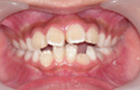

| 症状 | 前歯が飛び出していてお口が閉じにくい状態です。 身体が傾いてしまっています。 |

| 原因 | 舌の悪い癖や生活習慣から、歯列が狭くなり、前歯が飛び出してきました。 |

治療前-治療後

飛び出して持ち上がってしまっていた前歯が降りてきました。

これで永久歯を抜かないで治療することができるようになりました。飛び出していた前歯がだんだん咬みあってきました。